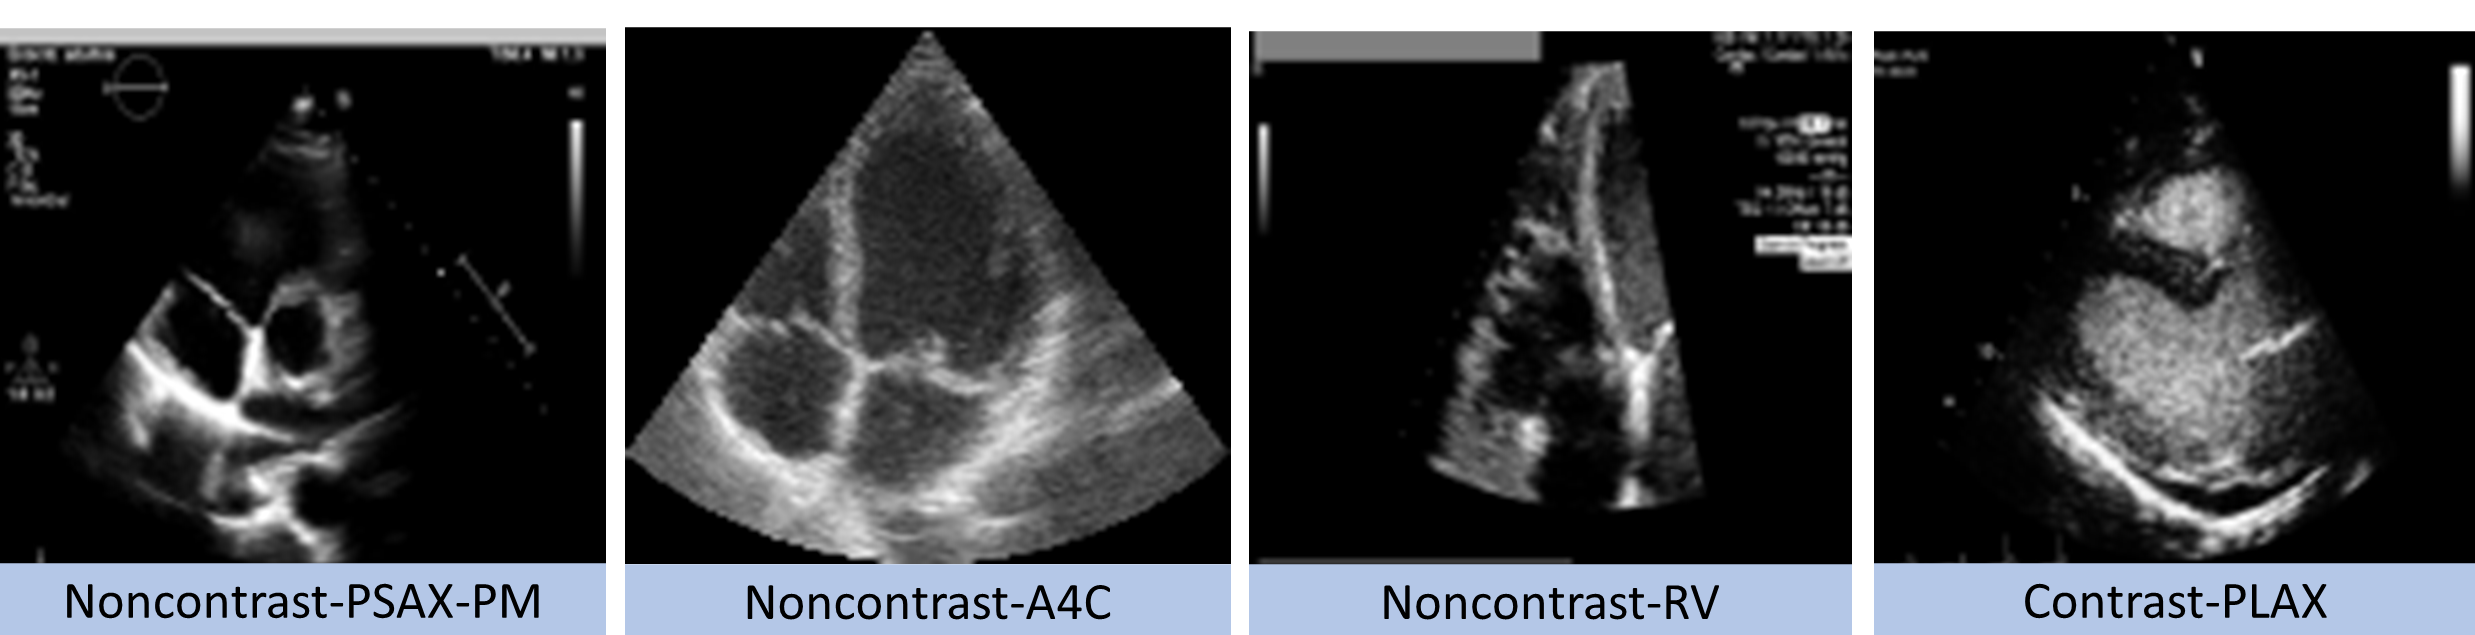

Figure 1: Examples of different views from WASE, CAMUS, Medstar, StG datasets.

In this paper we address the problem of building an echo view classifier model with multiple datasets from different sites (see Fig. 1) that are not simultaneously available and have different, overlapping sets of labels. To this end, we build upon [23], and mitigate the “unqualified expert” problem by weighing the contribution of each branch by a learnt in-distribution (i.d.) score. This minimises the influence of logits which are o.o.d. for a given input image, while maximising the i.d. logits. Our weighting improves transparency as the contribution of each model is known during inference, indicating the similarity between input data and different training sets. Our method has the benefit of using learnt features as input rather than images, which provides a simple workaround in cases where licensing prevents image sharing but not sharing of byproduct features.